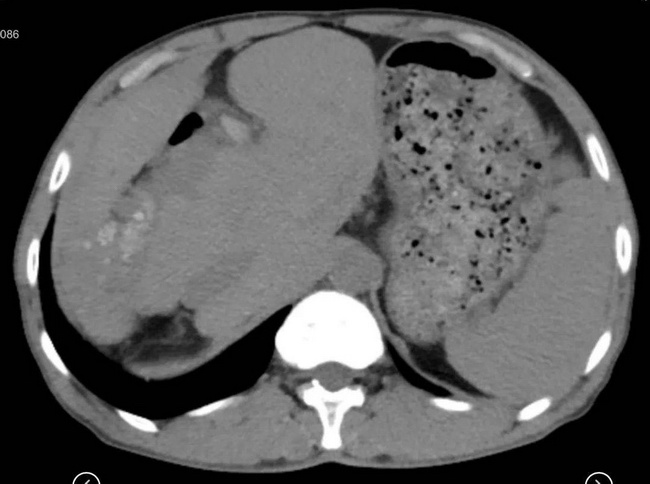

家住外地的王先生(化名)因反复发作腹痛、发热曾辗转于多家医院进行多次治疗,症状依然不见缓解。近日来哈医大四院就诊,影像学检查提示患者肝左叶及肝右叶内多发结石,伴相应胆管扩张,肝外胆管扩张,肝左、右叶(Ⅱ-Ⅷ段)萎缩,尾状叶(Ⅰ段)脉管结构正常,并明显代偿性增生,患者肝功能正常,诊断肝内胆管结石,肝脏萎缩增生综合征,肝外胆管扩张症,胆囊结石,胆囊炎。经过完善的术前评估及充分的术前准备,徐力善教授和杨冬冬教授成功为患者实施了肝脏次全切除(切除肝脏Ⅱ-Ⅷ段,仅保留Ⅰ段),肝外胆管切除,胆肠吻合术,现患者恢复良好。

正常人肝脏分为8个段,切除任何7个段都会导致患者残肝体积不足,患者无法存活。但该病人因疾病导致肝脏左右叶明显萎缩,尾状叶明显增生,代偿了其他肝段的肝脏功能,使仅保留1个肝段(尾状叶)成为可能。该手术难度极大,技术要求极高:需要完整切除病变的肝脏组织及全部肝外胆管,否则容易出现疾病复发甚至病变胆管癌变;此外,还必须保留尾状叶的所有脉管结构,否则将导致残肝血供不足或胆汁引流不畅,引起肝衰竭。